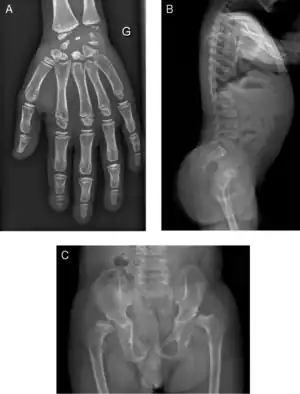

| Radiograph of a WRS child presenting with dysplastic bone growth in various regions of the body. | |

Initially, patients with neonatal or early-childhood onset diabetes are possible candidates for having Wolcott–Rallison syndrome.[1] The other features include multiple epiphyseal dysplasia, osteopenia, intellectual disability, and hepatic and renal dysfunction.[1] Patients having features that suggest Wolcott–Rallison syndrome can be referred for genetics testing. The key way to test for this disease is through genetic testing for EIKF2AK3 mutations.[7] Molecular genetic analysis can be done for the patient and the parents to test for inherited or de novo mutations. It can also show whether the patient's parents are heterozygotes or homozygotes for the normal genotype.[4] X-rays can show bone age in relation to actual age. In typical WRS patients the bone age is a few years less than the chronological age.[4][5][8][9] Hypothyroidism is rare in WRS patients but can occur.[4]